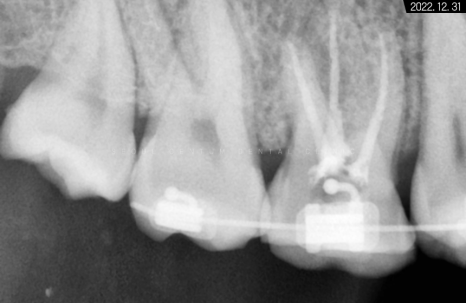

보통 어금니는 뿌리가 3~4개인 경우가 많아

신경 치료 시간이 조금 더 오래 걸리고

뿌리 형태도 휘어진 곳이 많다보니

앞니보다 난도 높은 술기에 해당합니다.

*기다란 막대기는 뿌리 끝 길이를

측정하기 위해 사용한 도구입니다.

교합면 우식을 제거하면서 근관 입구에 접근 후

근관장 길이 측정과 오염원 소파 및

소독 재료를 이용해서

근관을 멸균 상태로 만들고

그 후 안정 물질로 뿌리 끝까지

꼼꼼하게 메꿔드렸습니다.

그렇게 해서 3개의 뿌리가

흰색으로 잘 완성된 것을 볼 수 있습니다.

충전재로 잘 채워져 있고

레진으로 밀봉까지 마무리해두어서

하얗게 보이고 있는 것입니다.

다행히 뿌리가 막혀있지 않고